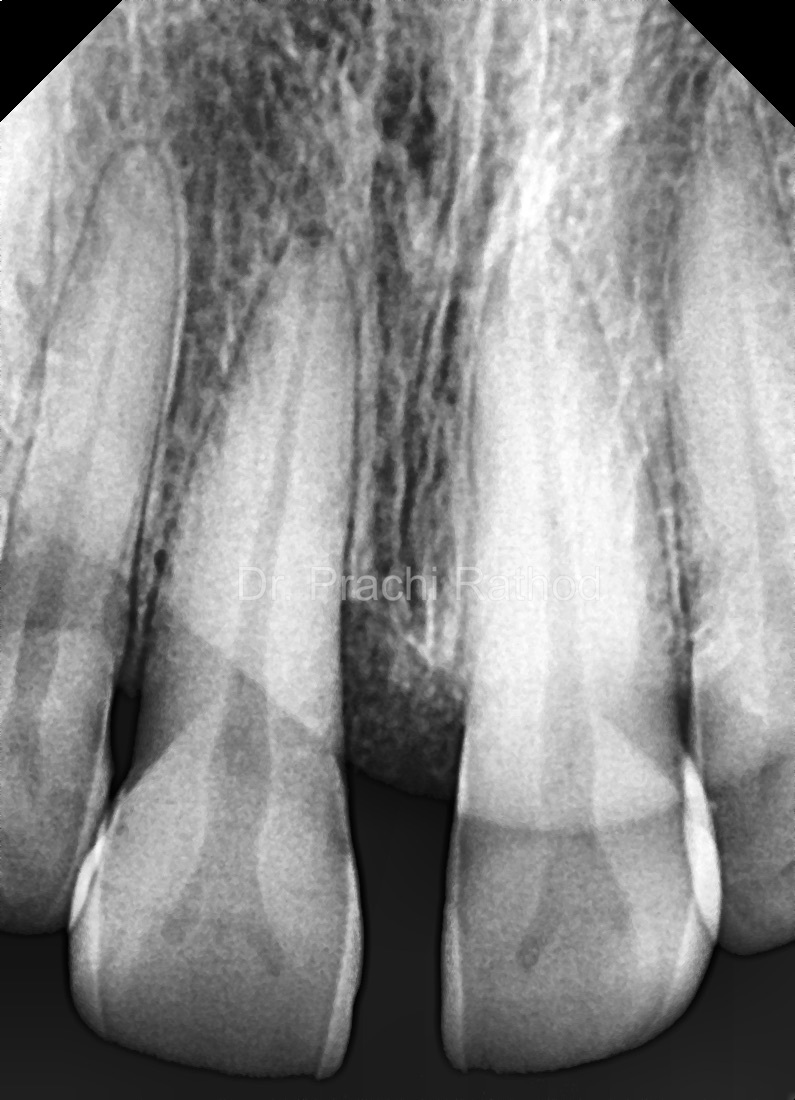

3 month Post Op RVG